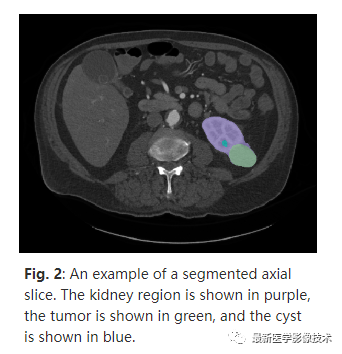

大体上,注释过程如下:首先学员在每个感兴趣区域周围放置 3D 边界框,然后,这些相同的受训人员在每个感兴趣区域周围放置 2D 轮廓。如有任何疑问,请咨询专家。轮廓注释经过后处理以生成分割(如图 2所示),分割由受训人员审查,并根据需要进行小幅修改,该分割任务训练了基线 nnU-Net 模型,专家根据需要进一步审查标签和交叉验证预测之间一致性较低的案例。